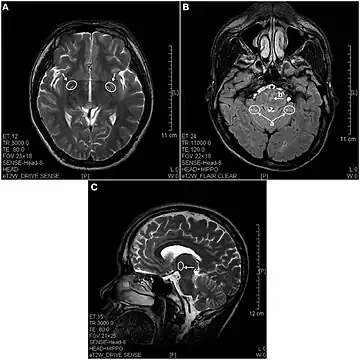

In 2013 a study using magnetic resonance imaging showed brain lesions in ketamine addicts (using from 0.2g twice a week up to 1g daily for 0.5 up to 12 years) with severity depending on the duration of addiction and daily intake of ketamine. Cortical atrophy and holes in superficial white matter are seen early on. After 4 years of addiction lesions spread throughout the brain and damage is evident in the pons and other deeper brain structures.[17]

- ↑ Wang C, Zheng D, Xu J, Lam W, Yew DT (2013). "Brain damages in ketamine addicts as revealed by magnetic resonance imaging". Frontiers in Neuroanatomy. 7 (23): 23. doi:10.3389/fnana.2013.00023. PMC 3713393. PMID 23882190.